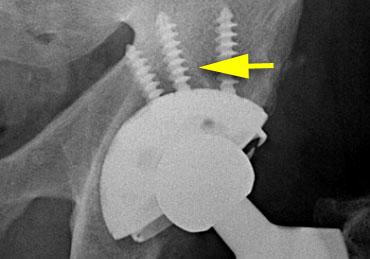

The case on the left is for several reasons not ideal :

– Vị trí cup quá cao và quá nghiêng về phía ngoài.

– Độ nghiêng sang bên quá nhiều.

– Lượng xi măng chèn lấp quá nhiều.

– Các vít được đặt quá nằm ngang (ứng suất quá lớn).

– Vùng thấu quang ở vùng II và III > 2 mm.

Đặc biệt, vùng thấu quang ở các khu vực này rất gợi ý đến tình trạng lỏng khớp.

Trong quá trình theo dõi, sự di chuyển lên trên kèm theo độ nghiêng tăng dần được ghi nhận, gây ra gãy vít cố định.